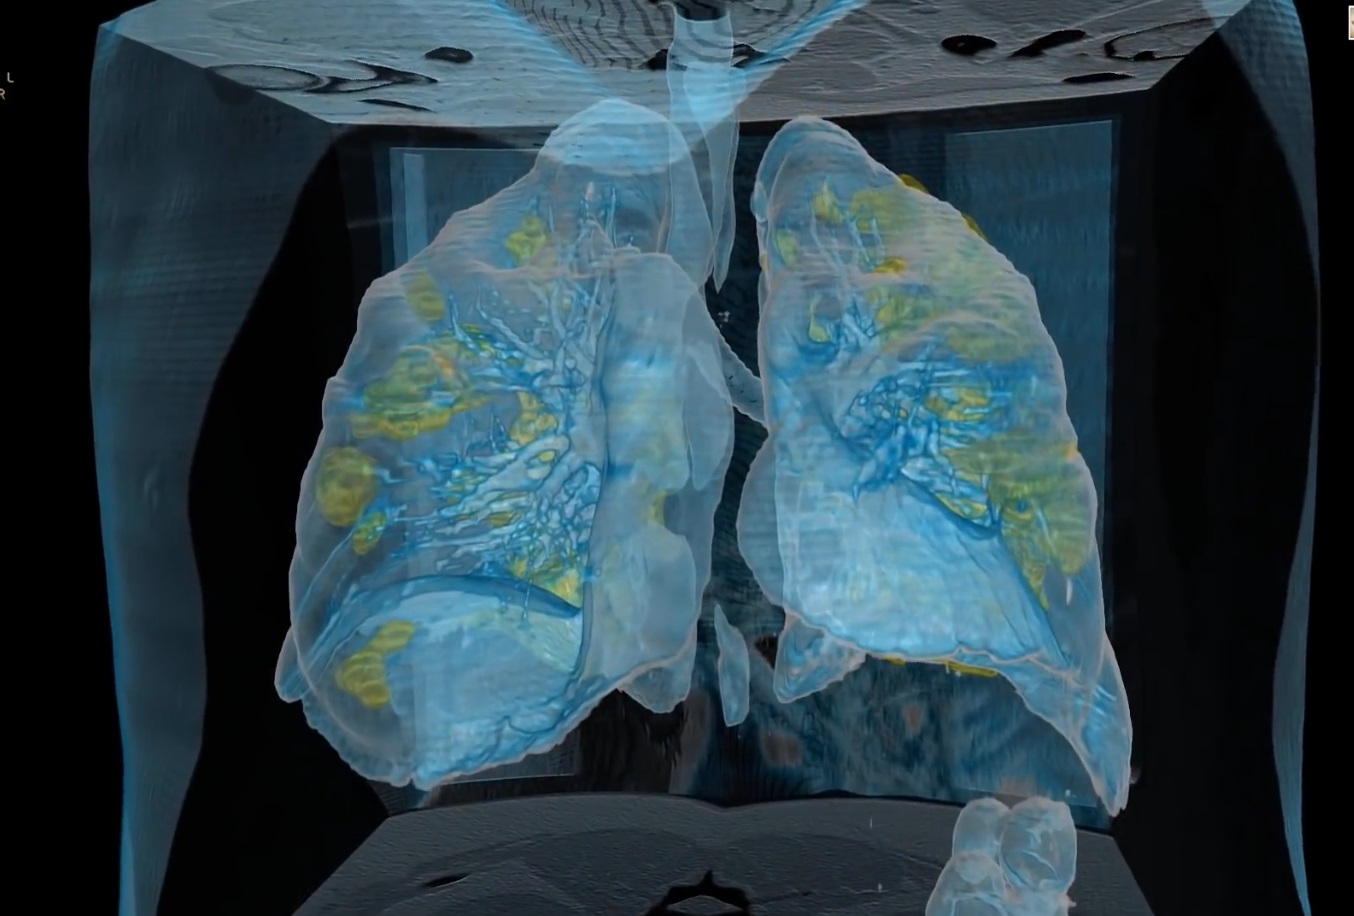

Поражение легких является одним из основных симптомов коронавируса (COVID-19). В данной статье представлены фото рентгеновских снимков, которые позволяют визуально оценить состояние легких при этом заболевании.

На фотографиях рентгеновских снимков видно, как вирус воздействует на легочную ткань. Характерные признаки поражения легких включают пятна, инфильтраты и наличие жидкости внутри легочных альвеол.

Фото рентгеновских снимков помогают врачам и специалистам визуально определить степень поражения легких и принять соответствующие меры лечения и поддержки пациента.